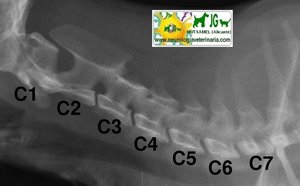

Radiografía columna cervical canina. Proyección ventrodorsal |